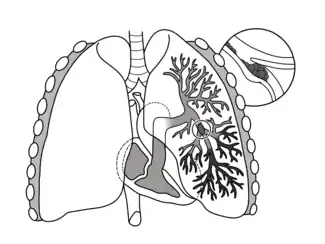

| A lung illustration depicting a pulmonary embolism as a thrombus (blood clot) that has travelled from another region of the body, causes occlusion of the pulmonary bronchial artery, leading to arterial thrombosis of the superior and inferior lobes in the left lung | |